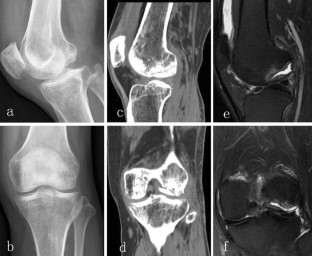

Fig. 1